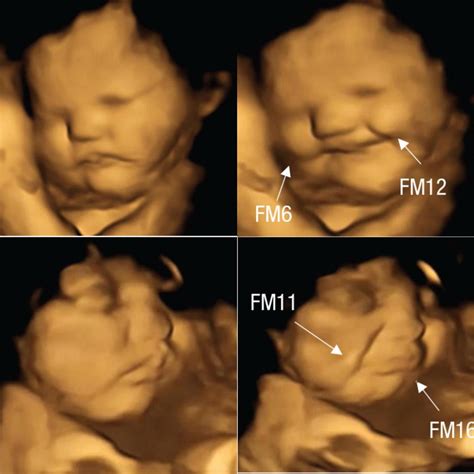

Schlaf-Wach-Rhythmus und Mimik

Langsam pendelt sich in der 21. SSW bei Ihrem Nachwuchs ein gewisser Schlaf-Wach-Rhythmus ein. Das Baby hat sogar schon eine Lieblingsposition beim Schlafen. Darüber hinaus entwickeln sich in der 21. SSW Mimik und Gestik. Die Augenbrauen wachsen, um die Mimik zu unterstützen, und zusätzlich zum feinen Lanugohaar sprießen auch Wimpern und Kopfhaare, die als Terminalbehaarung bezeichnet werden.

Die Feindiagnostik bietet eine noch genauere Analyse der kindlichen Entwicklung und wird bei Auffälligkeiten oder erhöhtem Risiko für Anomalien durchgeführt. 3D-Ultraschall liefert detaillierte, dreidimensionale Bilder des Babys.